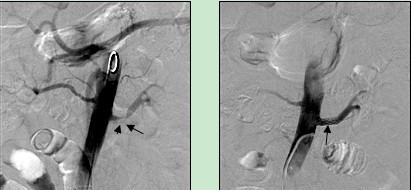

23岁反复咯血患者,因在外院拒绝手术切除右肺来我院就诊,造影显示右肺支气管动脉畸形(甲状颈干供血),经栓塞后畸形血管消失。